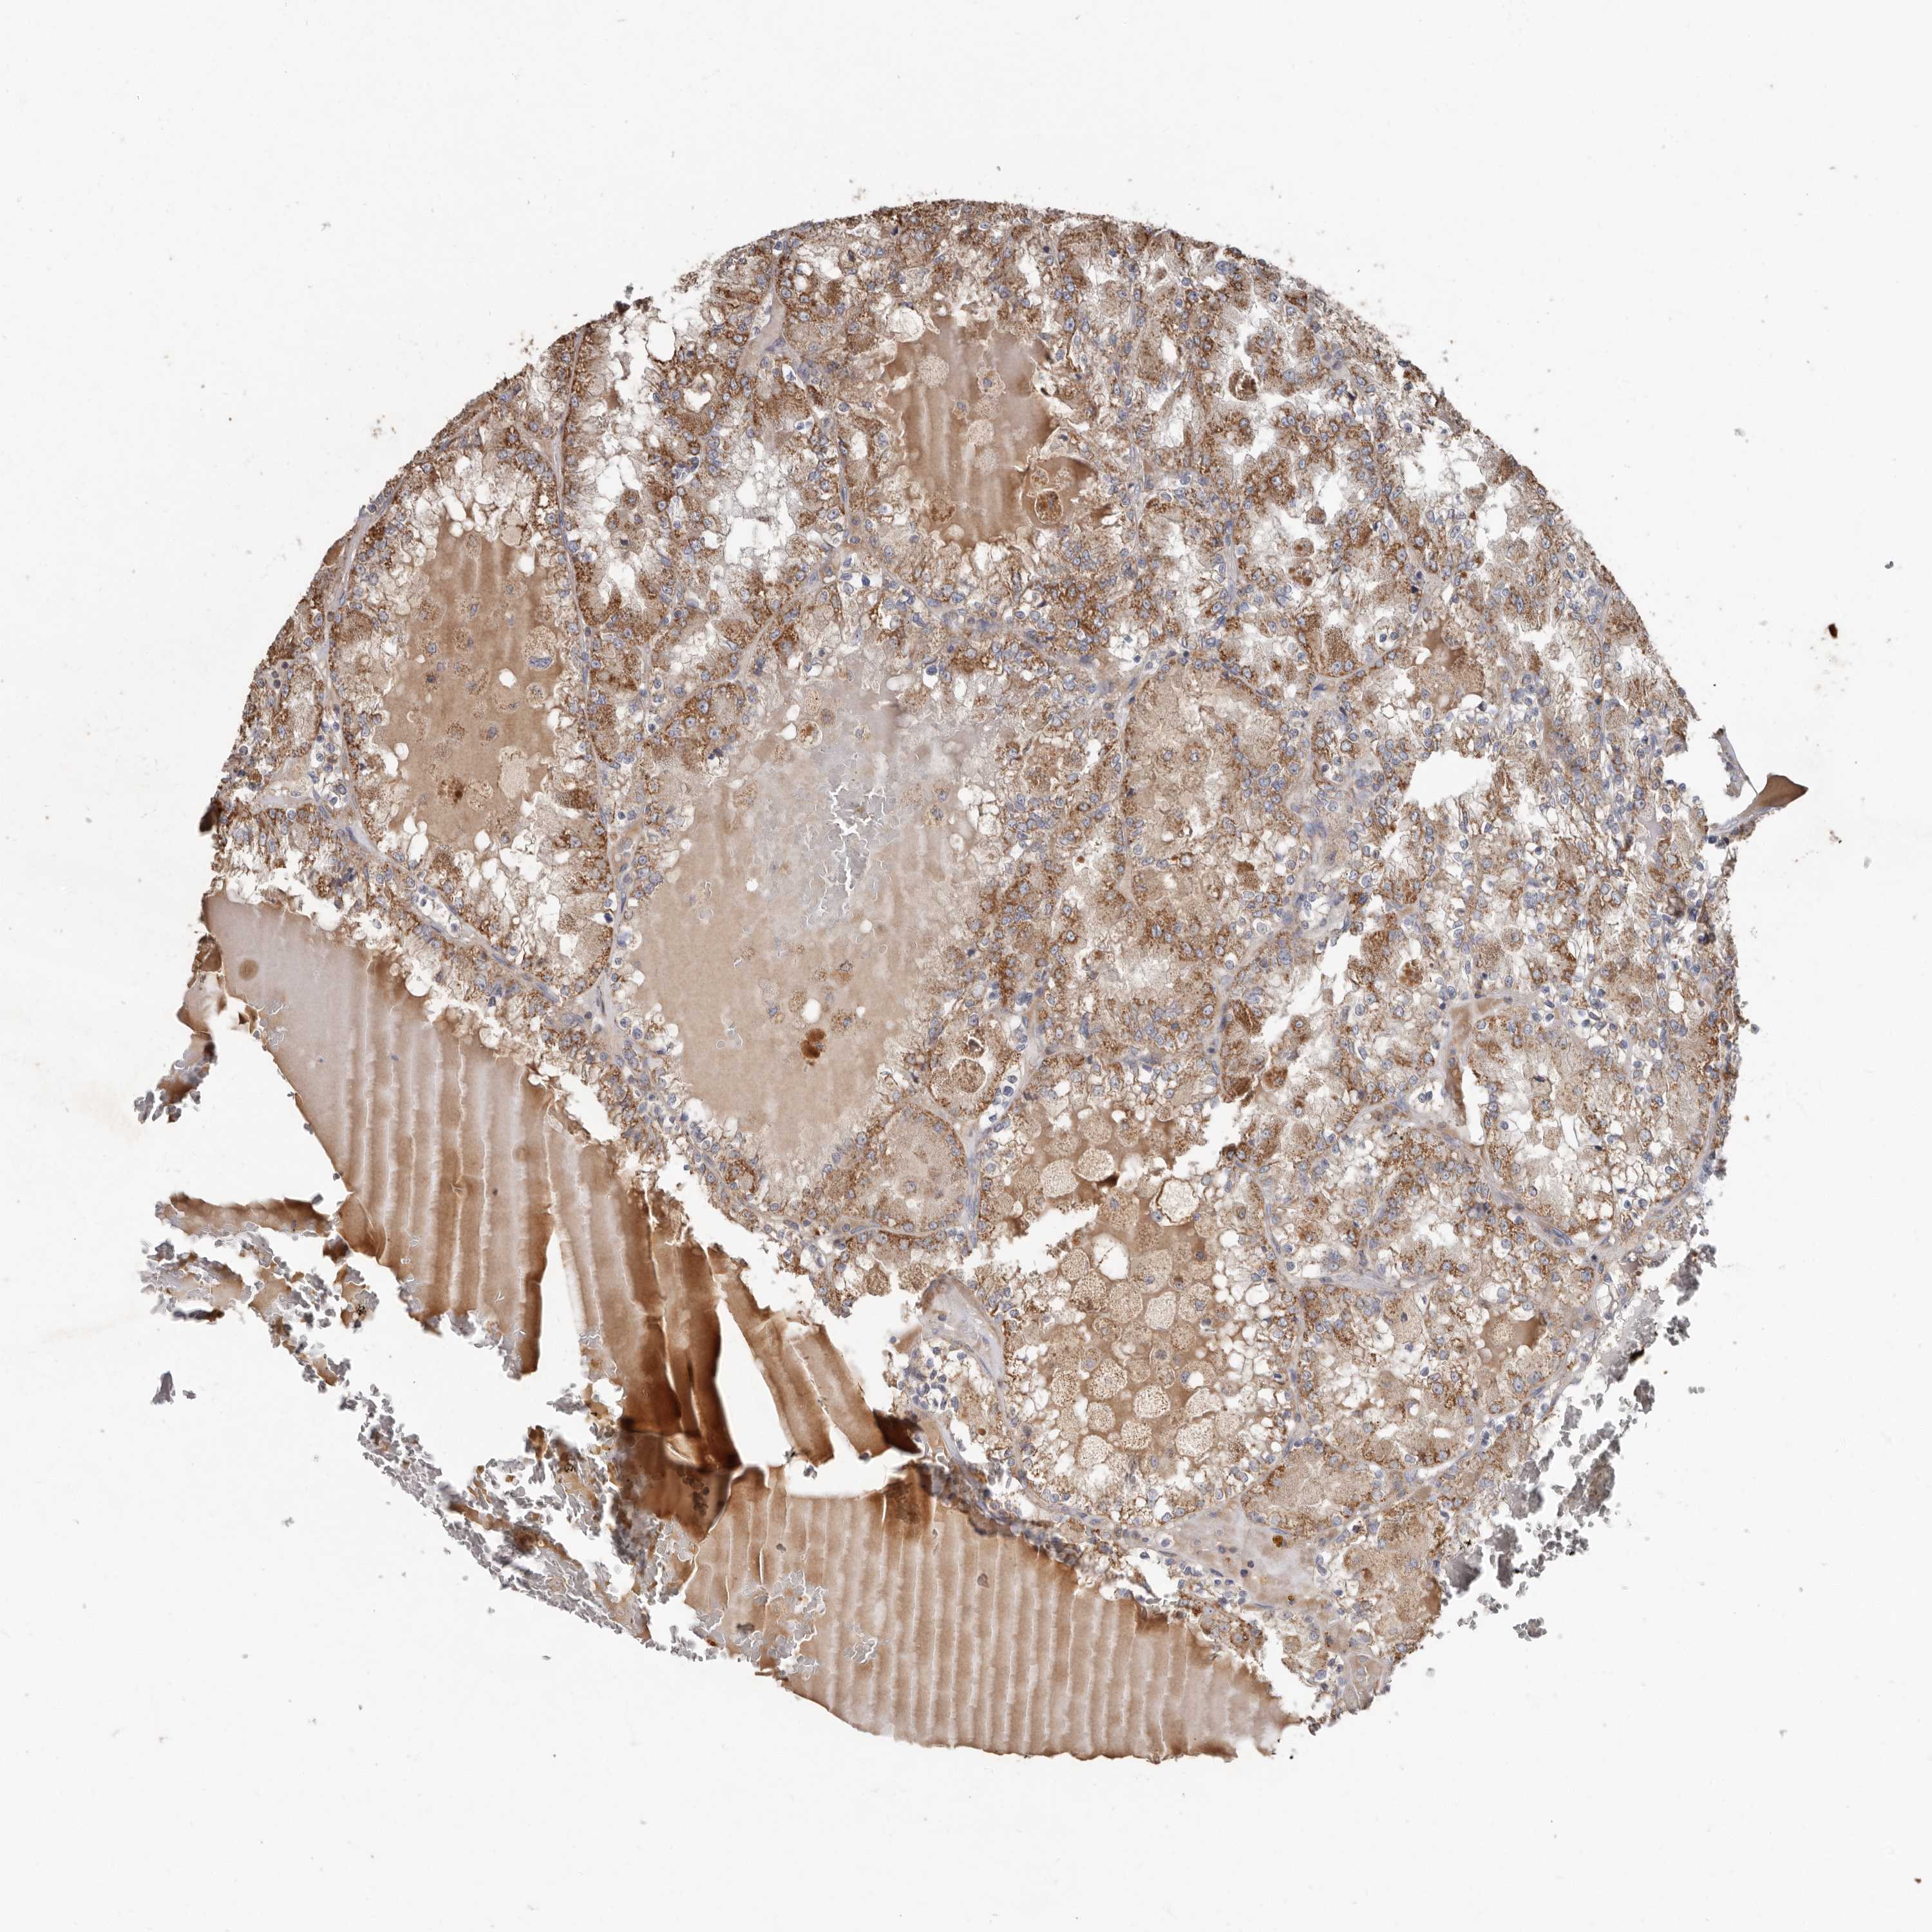

KIDNEY RENAL CLEAR CELL CARCINOMA (VALIDATION) - Interactive survival scatter ploti

The Survival Scatter plot shows the clinical status (i.e. dead or alive) for all individuals in the patient cohort, based on the same data that underlies the corresponding Kaplan-Meier plots. Patients that are alive at last time for follow-up are shown in blue and patients who have died during the study are shown in red.

The x-axis shows the expression levels (FPKM) of the investigated gene in the tumor tissue at the time of diagnosis. The y-axis shows the follow-up time after diagnosis (years). Both axes are complimented with kernel density curves demonstrating the data density over the axes. The top density plot shows the expression levels (FPKM) distribution among dead (red) and alive patients (blue). The right density plot shows the data density of the survived years of dead patients with high and low expression levels respectively, stratified using the cutoff indicated by the vertical dashed line through the Survival Scatter plot. This cutoff is automatically defined based on the FPKM cutoff that minimizes the p-score. The cutoff can be changed by dragging the vertical line or by entering a cutoff value in the square labeled "Current cut-off".

Under the Survival Scatter plot the p-score landscape (black curve; left axis) is shown together with dead median separation (red curve; right axis). Dead median separation is the difference in median mRNA expression between patients who have died with high and low expression, respectively. It is calculated as follows: median FPKM expression of dead patients with high expression - median FPKM expression of dead patients with low expression. This is intended to aid the user in visually exploring custom cutoffs and the associated p-scores and dead median separation.

Individual patient data is displayed and can be filtered by clicking on one or more of the category buttons on the top of the page. Categories describing expression level and patient information include: high, low, alive, dead, female, male and tumor stages. The scale of the x-axis can be toggled between linear and log-scale by clicking on the "x log" button. Mouse-over function shows TCGA ID, patient information and mRNA expression (FPKM) for each patient.

& Survival analysisi

Kaplan-Meier plots summarize results from analysis of correlation between mRNA expression level and patient survival. Patients were divided based on level of expression into one of the two groups "low" (under cut off) or "high" (over cut off). X-axis shows time for survival (years) and y-axis shows the probability of survival, where 1.0 corresponds to 100 percent.

KIF26B is not prognostic in Kidney Renal Clear Cell Carcinoma (validation)

TCGA RNA samplesi

RNA-seq data is reported as average FPKM (number Fragments Per Kilobase of exon per Million reads), generated by the The Cancer Genome Atlas (TCGA) .

Normal distribution across the dataset is visualized with box plots, shown as median and 25th and 75th percentiles. Points are displayed as outliers if they are above or below 1.5 times the interquartile range. FPKM values of the individual samples are presented next to the box plot.

Average pTPM 0.8

Number of samples 100